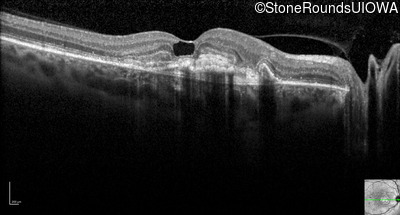

Optical Coherence Tomography - Right - 20/250

Exemplar / OCT Stack

Infrared Fundus Photograph - Right - 20/250

Exemplar